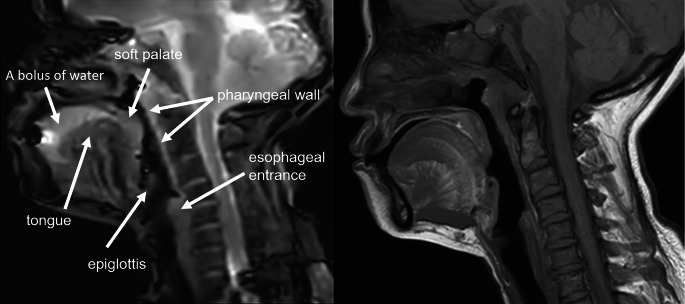

Cine magnetic resonance imaging (Cine-MRI) may evaluate the swallowing function and locations of patients with dysphagia, which requires very fast imaging speed. Compressed sensing is a technique that allows for faster MRI imaging by sampling fewer data points and reconstructing the image via optimization techniques, crucial for capturing the rapid movements involved in swallowing. This study aimed to analyze swallowing function and locations in patients with head and neck cancer and healthy individuals using Cine-MRI based on compressed sensing. This comparative study enrolled 36 patients with dysphagia and 10 healthy controls at the Department of Radiology, Yunnan Cancer Hospital between June 2020 and January 2021. Significant correlations were found between primary tumor location and Cine-MRI parameters, and between swallowing function and Cine-MRI parameters. The areas under the receiver operating characteristic curve for the combined Cine-MRI-related parameters in predicting mild and severe dysphagia were 0.806 (95% CI: 0.662-0.949). Cine-MRI with compressed sensing may identify swallowing function and abnormal stages of the physiologic swallowing process in patients with dysphagia after treatment.